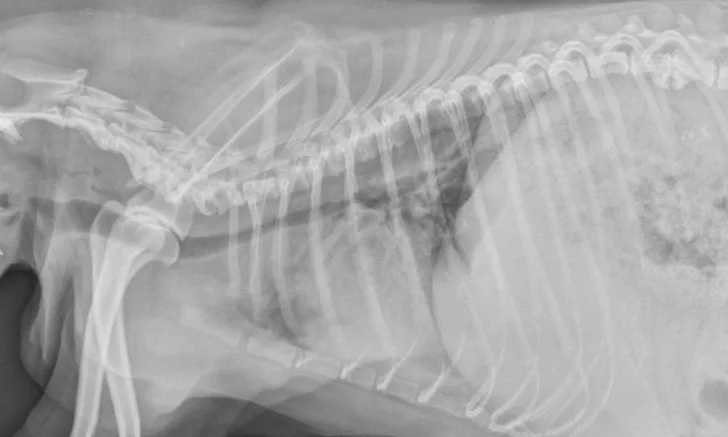

On examination, the dog was panting with expiratory effort and crackles auscultated diffusely. She exhibited an occasional goose-honking cough and retch. Her body temperature was normal. Radiography (Figures 1 and 2), fluoroscopy (Figure 3), and bronchoscopy (Figures 4 and 5) were performed.

FIGURE 1

Left lateral radiograph showing dynamic collapse of the intrathoracic trachea from the level of the thoracic inlet to the mainstem bronchi. A small amount of esophageal gas is observed (asterisk), and the lungs are hypoinflated, which is likely secondary to increased respiratory effort. Mild, generalized cardiomegaly and hepatomegaly are also evident in the thorax (arrows) and abdomen (arrowheads), respectively.